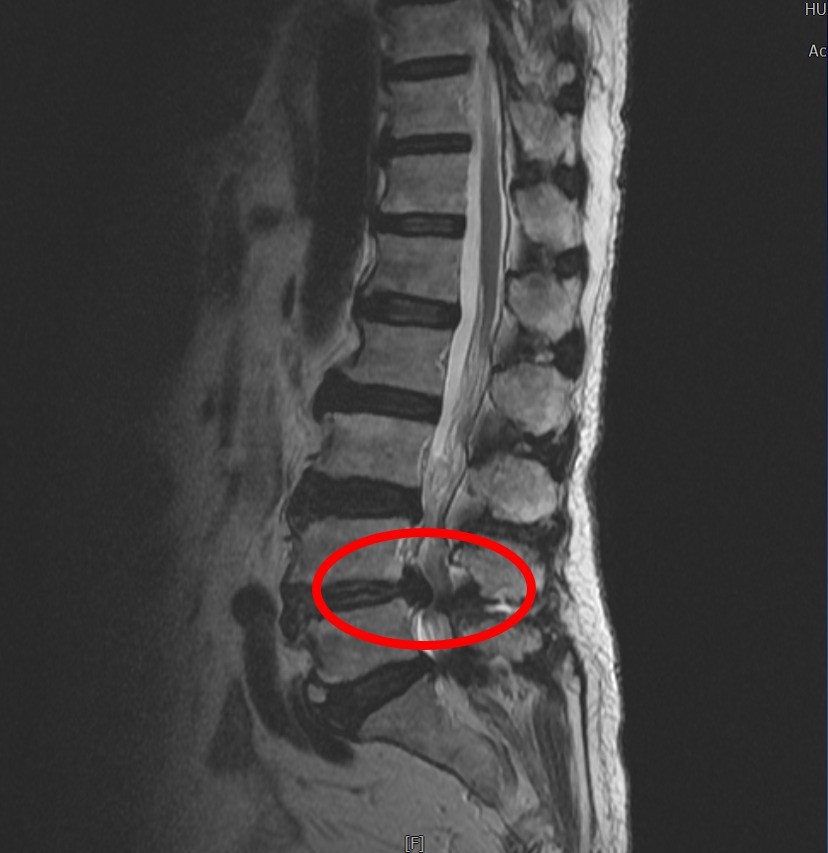

經腰椎X光及磁振造影(MRI)檢查,可看到她的腰椎明顯滑脫,第四、第五節腰椎椎管已嚴重狹窄,壓迫神經,於是建議她接受微創腰椎減壓手術治療。而她的術後恢復良好,在手術隔天就可以自行下床活動,雙腳的麻痛感也明顯減輕。

經核磁造影檢查,造成婦人下背疼痛的主因是腰椎第四/五節嚴重神經狹窄。

脊椎退化是造成老年人活動受限的三大常見原因,隨着年紀增加,脊椎會發生退化性的病變,這些退化性的病變如果發生在脊椎椎管周圍空間,就會導致椎管狹窄,壓迫椎管內的神經而產生痠痛、麻木感等不適症狀。老婦人因為神經幾乎全被壓扁,這也是最近一年來她飽受疼痛折磨的主要原因。